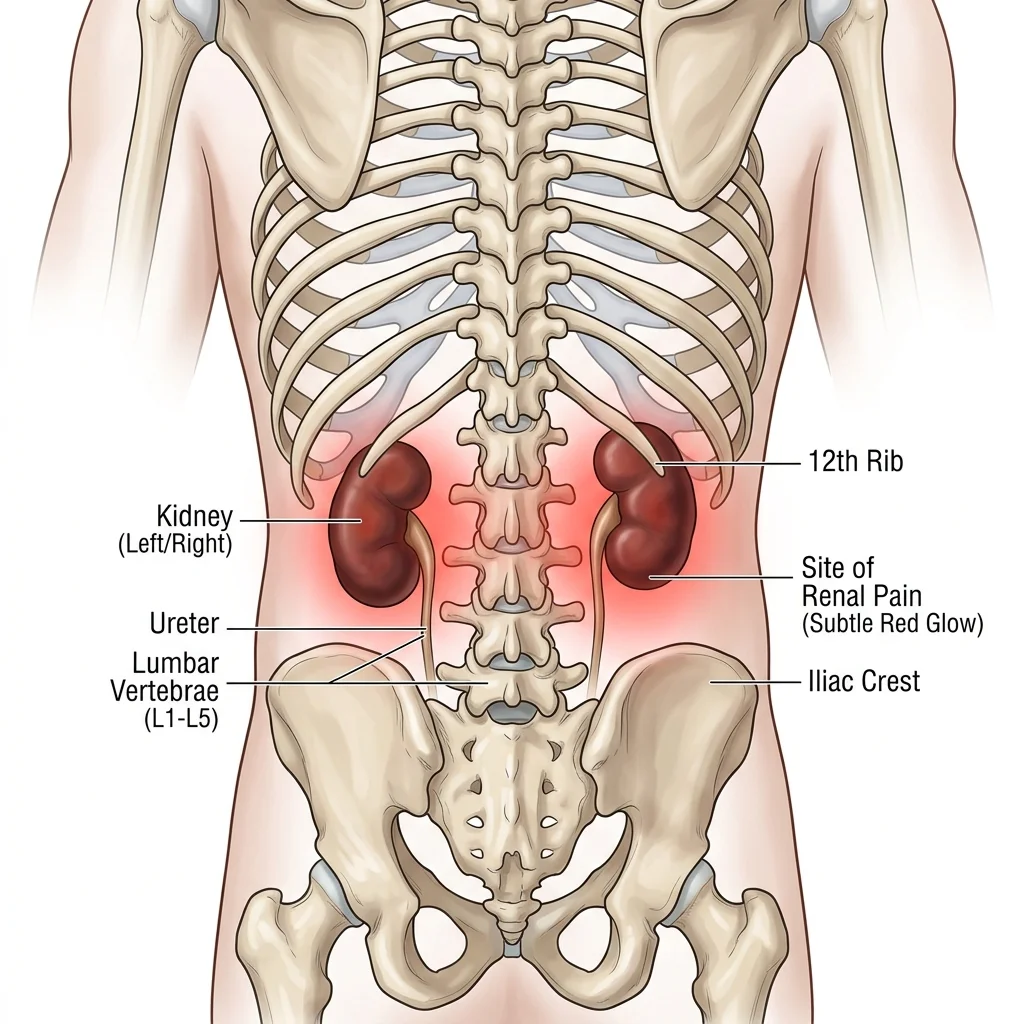

Sentir dor nas costas e não saber se é muscular ou dos rins é comum. Aprenda a identificar os sinais.

Entenda as 10 principais causas de dor nos rins e como identificar a localização exata da dor.

Saiba identificar se aquela dor lombar é muscular ou um alerta dos seus rins. Guia completo.

Entenda a diferença entre a dor muscular e a terrível cólica renal. Descubra os exames necessários.